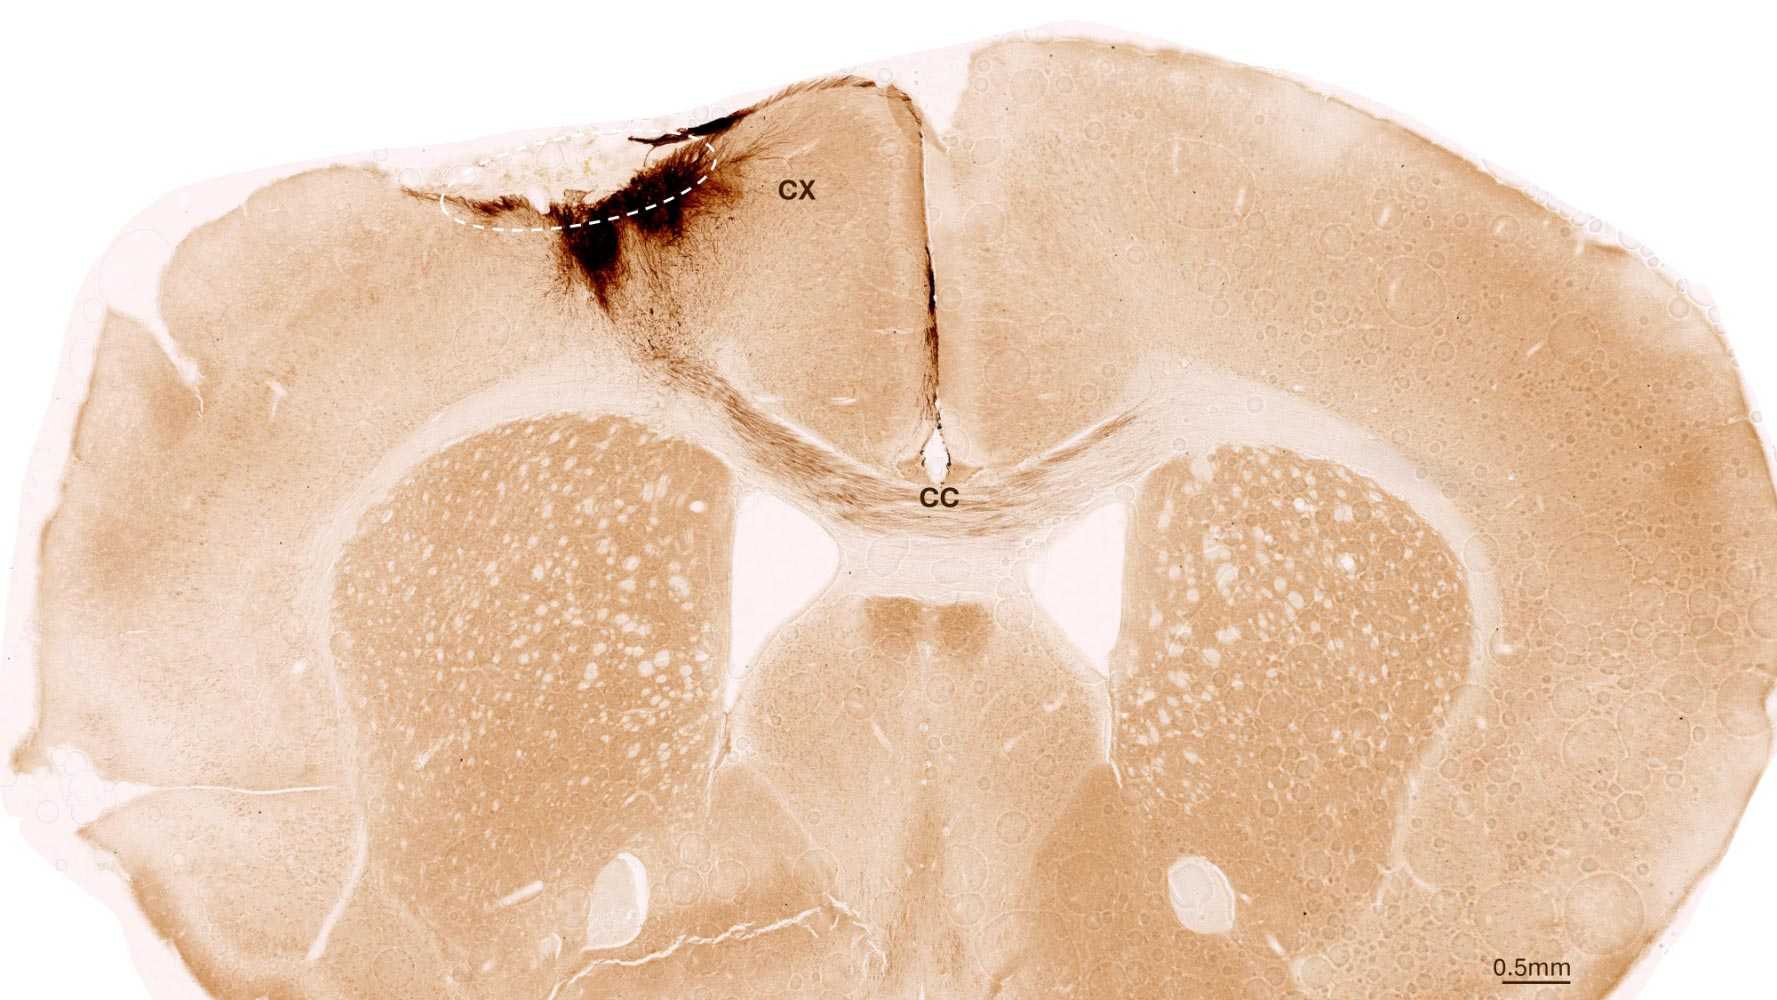

Через неделю ученые трансплантировали стволовые клетки в поврежденную область мозга. Они следили за результатами, используя различные визуализирующие и биохимические методы. Исследователи обнаружили, что стволовые клетки выживали в течение всего периода наблюдения — пяти недель. Большинство из них превратились в нейроны, взаимодействующие с уже существующими клетками мозга.

Исследователи обнаружили и другие признаки регенерации: образовывались новые кровеносные сосуды, уменьшались воспалительные процессы и улучшалась целостность гематоэнцефалического барьера. Трансплантация стволовых клеток у мышей также обратила двигательные нарушения, вызванные инсультом.